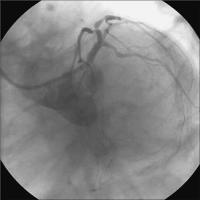

Vordilatation LAD

Abbildung 4: Vordilatation LAD mit 2,5/20-mm-Ballon - 16 atm.

Keywords: KardiologieKoronarangiographieVordilatation